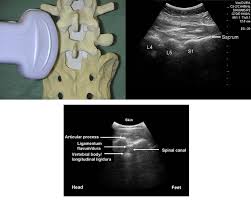

وبالإمكان خفض هذه الاحتمالية عندما يتم اختيار #المريض المناسب طبيا لهذا الإجراء وعندما يتم إجراء #التخدير_النصفي من قبل #طبيب_تخدير استشاري متمرس لديه المعرفة والقدرة على التعامل مع الحالات واستخدام الأشعة السينية او فوق الصوتية للحالات الصعبة

3️⃣اصابة العصب الدائم (متلازمة ذيل الفرس) Conus medullaris syndrome

وهو عبارة عن اصابة غير مكتملة للحبل الشوكي ولا تسبب #الشلل_النصفي وقد بينت دراسة فرنسية ان نسبة الإصابة بهذه المضاعفة تعتبر ضئيلة للغاية وهي ١ في كل ١٧٨٦٦٠ حالة مع العلم ان ٥٠٪ من الحالات كانت حالات #الولادة

١.وجود مرض في #الحبل_الشوكي

٤.تضيق قناة الحبل الشوكي